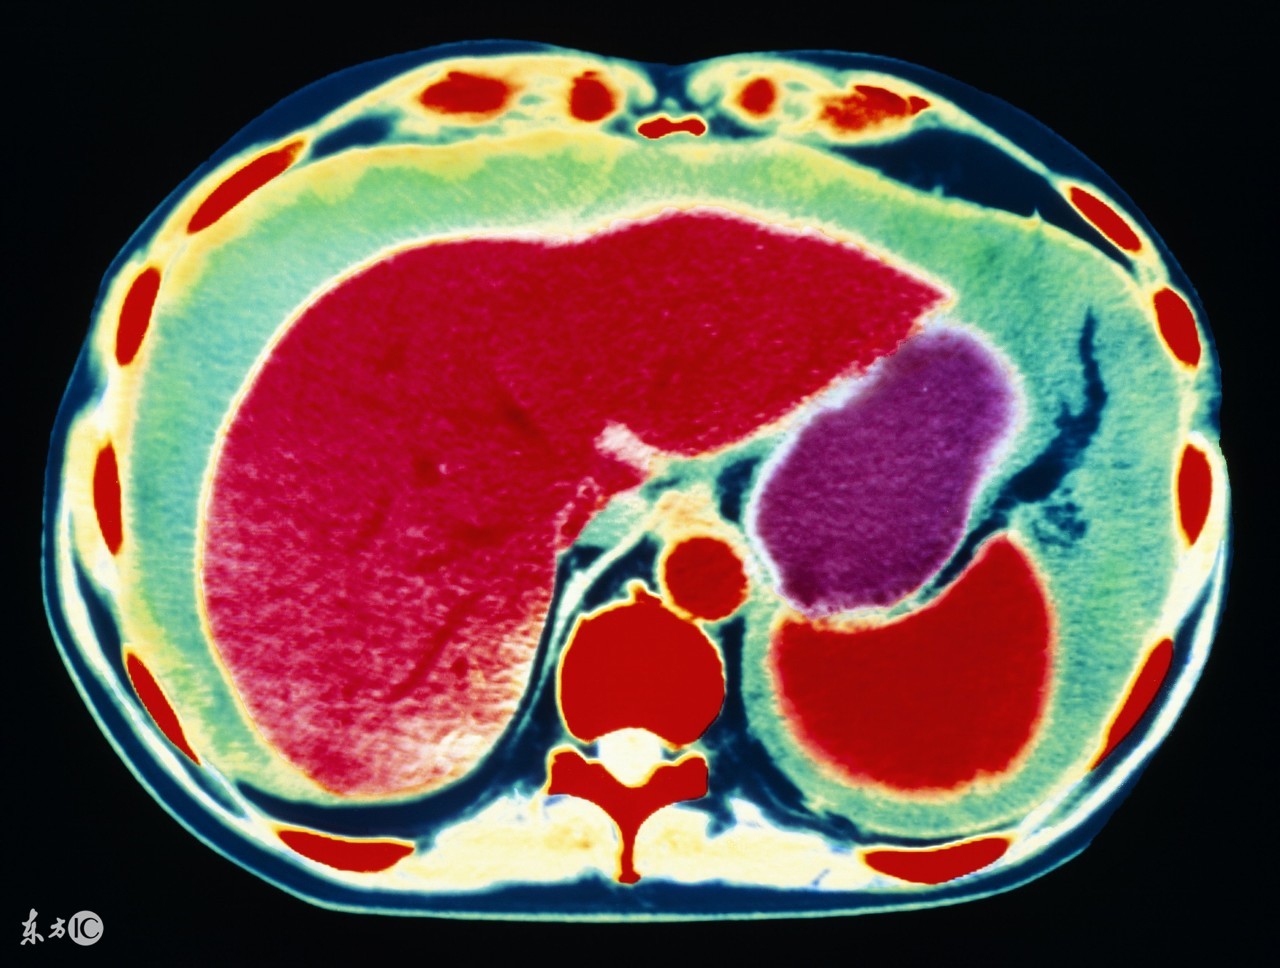

1、肝癌。前面说了,肝病是引起腹水最常见的原因,其中肝癌就是其一。原发性肝癌,发展到一定程度,合并腹水的可能性非常大,其实本质上仍是肝硬化所致,所以肝腹水就是肝硬化腹水。肝硬化时,肝细胞变性、坏死、纤维策划增生,肝内血管床受压、扭曲、变形、狭窄,阻塞了血管,使肝窦淤血,血流量大大降低,门静脉压力升高,同时,毛细血管静脉压力也升高,久而久之,胃肠道、肠系膜、腹膜等血液回流受阻,血管通透性升高,血液中的血浆成分外漏,形成了腹水。肝功能不合,肝脏不能合成白蛋白,低蛋白血症,由于血清白蛋白的降低,血管内胶体渗透压下降,血浆成分外渗而形成腹水。所以,不管什么肝病,到了肝硬化,肝功能不全的阶段,就可能形成腹水。

3、卵巢癌,包括输卵管癌、原发性腹膜癌,这三种癌症的治疗原则是一样的,这类癌症也是引起腹水的最常见原因之一,女性如果有大量的腹水,要首先排除卵巢癌可能,有针对性的重点查一查卵巢输卵管。